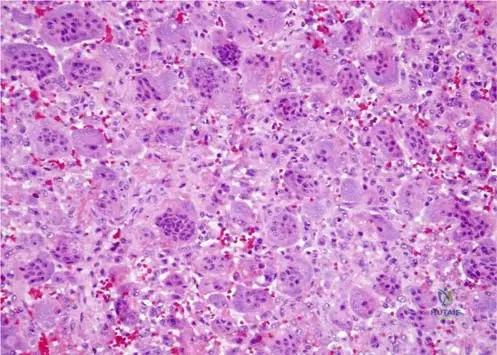

Rationale: The text and Fig. 8.23 describe enchondromas as having a "lobular growth pattern and hypocellular nature... The nuclei are uniform." This histological description is characteristic of a benign enchondroma, even if the lesion is painful or appears somewhat aggressive radiographically. The other options represent malignant tumors with different histological features.

Rationale: The text and Fig. 8.23 describe enchondromas as having "uniform nuclei," which is a histological feature of a benign lesion. Nuclear uniformity (lack of pleomorphism) is a critical indicator distinguishing benign cartilaginous lesions from malignant ones like chondrosarcoma. The other options are incorrect interpretations of this benign histological feature.

Rationale: The clinical context for Fig. 8.23 a, b explicitly states, "Low-power images demonstrate the lobular growth pattern and hypocellular nature of enchondromas." This directly answers the question. The other options describe growth patterns associated with other types of bone tumors (e.g., osteosarcoma, chondrosarcoma, fibrous dysplasia).

A 29-year-old female undergoes a biopsy of an intramedullary lesion in her proximal phalanx. The low-power histological examination reveals a lobular growth pattern with widely dispersed cells within the matrix. This description points to which characteristic of enchondromas?

Rationale: The clinical context for Fig. 8.23 a, b explicitly states, "Low-power images demonstrate the lobular growth pattern and hypocellular nature of enchondromas." Widely dispersed cells within the matrix is a description consistent with hypocellularity. The other options describe features not characteristic of benign enchondromas.